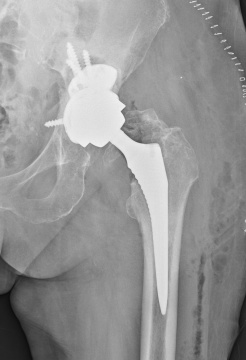

Tím II. ortopedicko – traumatologickej kliniky LF UK a UNB v Nemocnici sv. Cyrila a Metoda v Petržalke, pod vedením prednostu prof. MUDr. Borisa Šteňa, PhD. uskutočnil inovatívnu operáciu, počas revízie totálnej endoprotézy bedrového kĺbu. Inovácia spočíva v implantácii revízneho modulárneho komponentu.

Tento implantát novej generácie špeciálnych endoprotéz je určený pre operačnú liečbu zlyhaných endoprotéz pri rozsiahlych kostných defektoch. Išlo nielen o prvú operáciu na Slovensku, ale celkovo v poradí o štvrtú operáciu na svete s použitím tzv. „butress“ dlahy, vyrobenej z trabekulárneho titánu. Operácii sa úspešne podrobila 81 ročná pacientka s rozsiahlym kostným defektom v oblasti po implantácii jamky totálnej endoprotézy.

„S potešením môžem skonštatovať, že nám na pracovisku pri operačnej liečbe zlyhania totálnych umelých náhrad bedrových kĺbov pribudol inovatívny implantát. Máme tak k dispozícii viac možností na ošetrenie komplexných kostných defektov. Na rozdiel od predošlých implantátov, tieto vieme kombinovať ako čisto necementované alebo v kombinácii s kostným cementom a kostnými štepmi.“ uviedol Boris Šteňo, prednosta II. ortopedicko – traumatologickej kliniky LF UK a UNB. Rekonštrukcia veľkého kostného defektu na strane acetábula, teda v mieste implantácie jamky totálnej endoprotézy, býva vždy zložitá, niekedy žiaľ aj nemožná. Od tohto nového implantátu si naši odborníci sľubujú rozšírenie možnosti bezpečného použitia v revíznej endoprotetike, prípadne aj u pacientov po rozsiahlych kostných defektoch po zlomeninách panvy a acetábula.